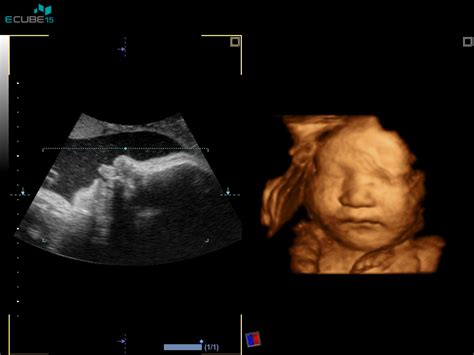

V 22. tednu nosečnosti otrok meri približno 25 cm in tehta okoli 400 gramov. Njegovi notranji organi so že na mestu, kosti notranjega ušesa pa so dovolj razvite, da že zelo dobro sliši. Kljub temu, da se koža še razvija in je še precej nagubana zaradi pomanjkanja podkožne maščobe, se njene plasti zaključujejo. V zobnih nastavkih se začnejo razvijati prvi mlečni zobje. Otrokove okončine so v pravilnih proporcih glede na telo, količina maščobnega tkiva pa se hitro povečuje, kar bo ključno za uravnavanje telesne temperature po rojstvu.